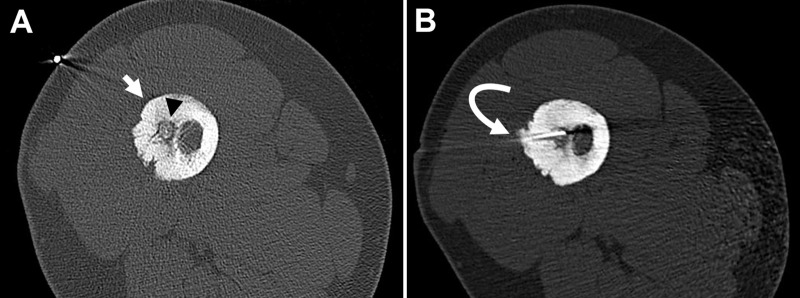

Materials and methods: In this retrospective cohort study all patients that were diagnosed with osteoid osteoma and treated using radiofrequency ablation between January 2014 and December 2022 were included. Pain was assessed using Visual Analog Scale (VAS) pre and post procedure. Technical success was established as positioning of the radiofrequency electrode in the nidus. Primary clinical success was defined as absence of pain after one radiofrequency session. All patients that required a second radiofrequency ablation were included in the overall clinical success group.

Results: During the studied period, 61 osteoid osteoma radiofrequency ablations were performed. Fiftyseven of them were included in this study, 32 were men and 25 female. Pre procedure median pain was 9 according to VAS score. Only 23 patients were treated as outpatient, the rest stayed in hospital for 24 hours. Median follow up time was 21,7 months (SD 8,3). Biopsy was performed in 52 patients. Technical success was accomplished in 57 patients (100%). Primary clinical success was 80,7% (46 patients). Those who continued with pain or had recurrence after a symptoms free period (11 patients), were treated with a second radiofrequency ablation, achieving an overall success rate of 94,7%. Only one patient suffered a minor complication (1,7%).